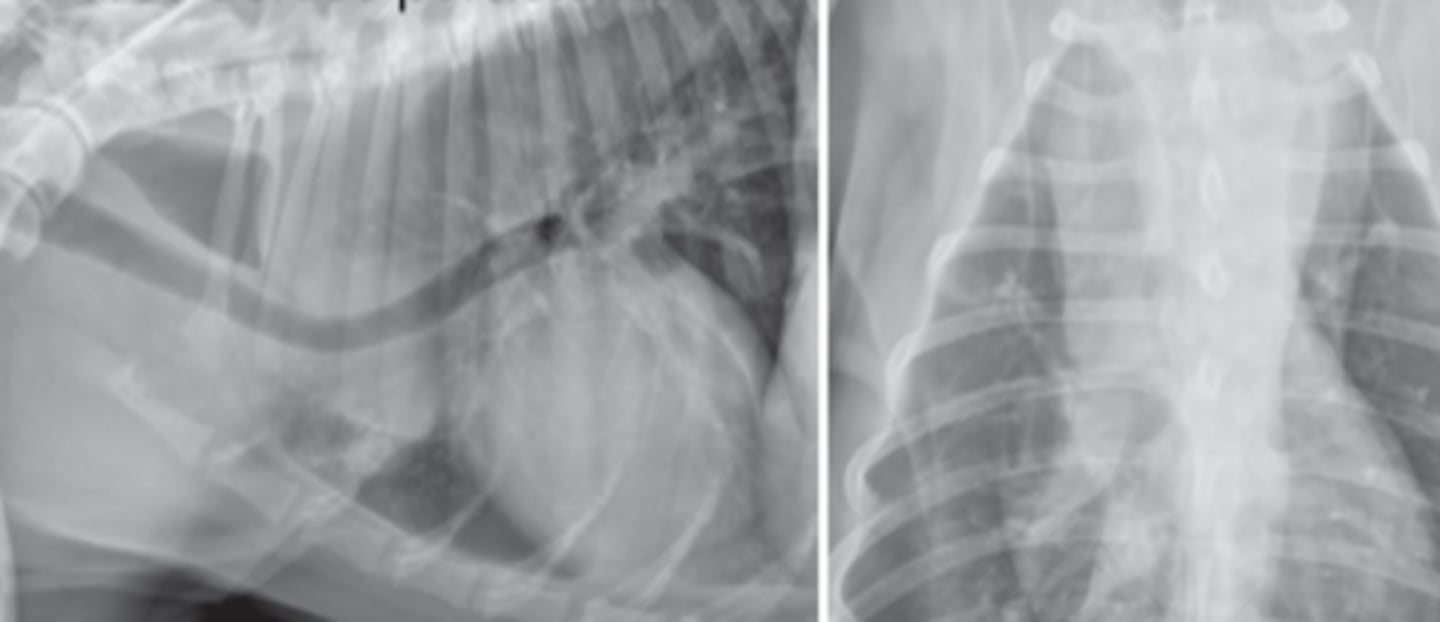

efusión pericárdica

patología:

hernia diafragmática peritoneopericardica